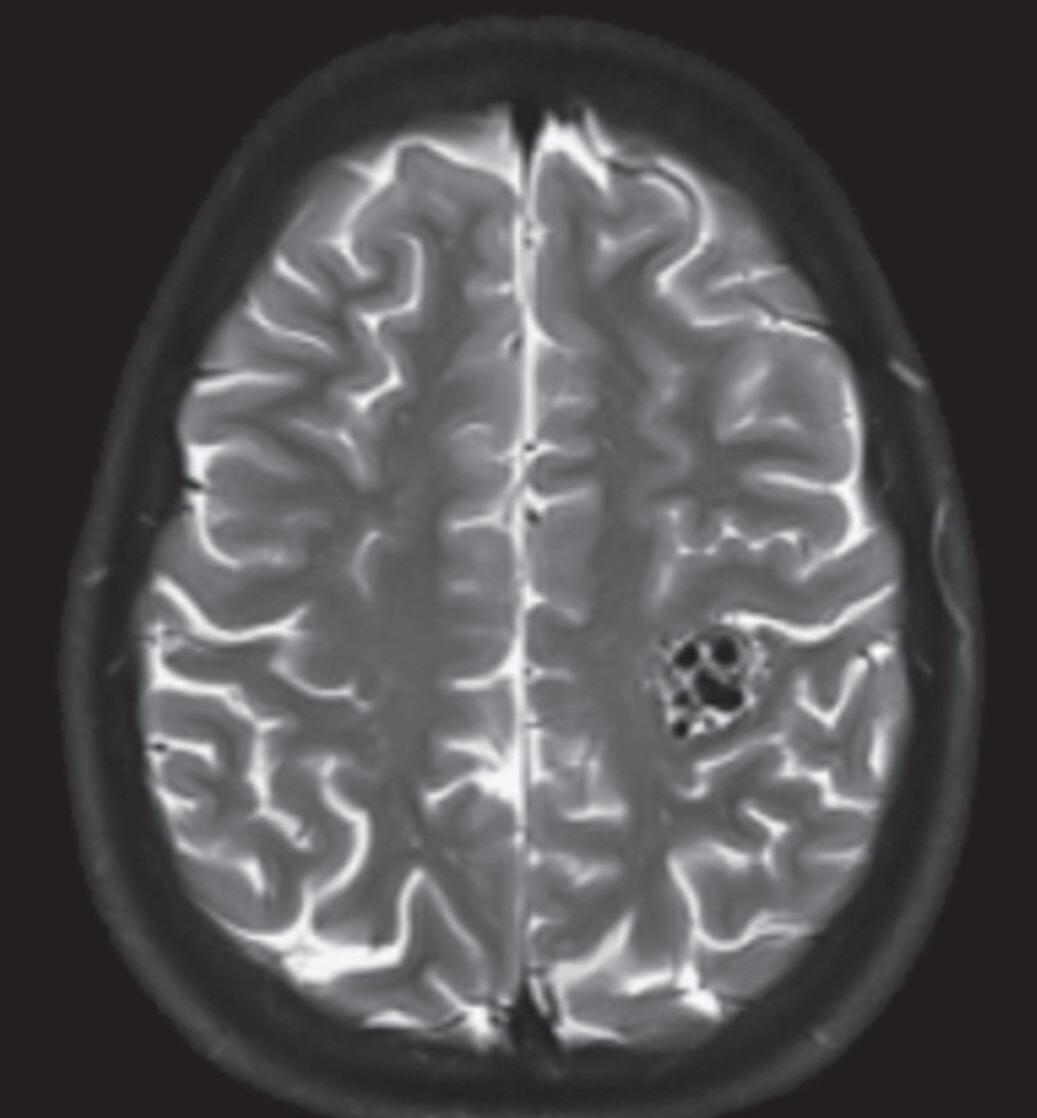

Fig. 1-9. RNM T2 em cortes (a) axial e (b) sagital. (c,d) Tractografia axial – sagital, demonstrando a posição de uma MAV não rota localizada na superfície basal do lobo frontal, nos giros orbitários e reto à direita (setas longas). Arteriografia digital cerebral com injeção de contraste via carótida direita, (e) AP e (f) em perfil demonstrando MAV nutrida por ramos da artéria cerebral média e cerebral anterior direita e drenagem para o seio sagital superior (seta curta).